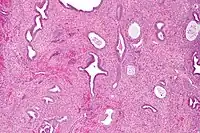

Endometrial polyps can be solitary or occur with others.[11] They are round or oval and measure between a few millimeters and several centimeters in diameter.[7][11] They are usually the same red/brown color of the surrounding endometrium although large ones can appear to be a darker red.[7] The polyps consist of dense, fibrous tissue (stroma), blood vessels and glandlike spaces lined with endometrial epithelium.[7] If they are pedunculated, they are attached by a thin stalk (pedicle). If they are sessile, they are connected by a flat base to the uterine wall.[11] Pedunculated polyps are more common than sessile ones.[4]